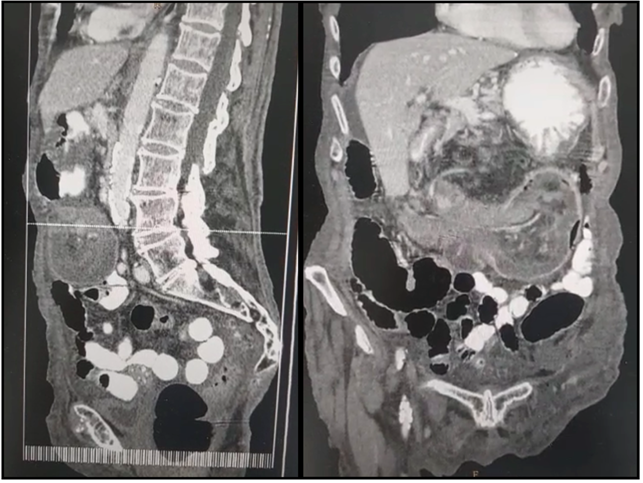

Tomografía abdominopélvica con contraste oral y endovenoso: Se observa derrame pleural bilateral. Por otra parte, a nivel centroabdominal y con extensión hacia flanco izquierdo se identifica extensa imagen redondeada con estructuras vasculares en su interior y contenido aéreo compatible con intususcepcion intestinal (invaginacion colocolónica) con una extensión aproximada de 10cm con refuerzo parietal ante la administración de contraste endovenoso. Presencia de moderado líquido libre multicompartimental, sin evidencia de niveles hidroaéreos.

IMAGEN 2. A) Corte sagital. B) Corte coronal evidenciando invaginación colocolónica.